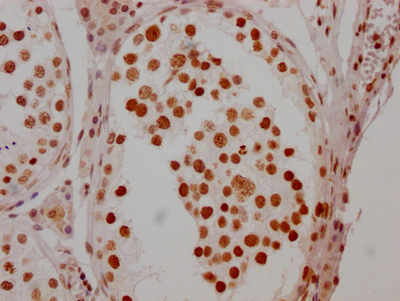

IHC image of CSB-RA279005A0HU diluted at 1:100 and staining in paraffin-embedded human testis tissue performed on a Leica BondTM system. After dewaxing and hydration, antigen retrieval was mediated by high pressure in a citrate buffer (pH 6.0). Section was blocked with 10% normal goat serum 30min at RT. Then primary antibody (1% BSA) was incubated at 4℃ overnight. The primary is detected by a Goat anti-rabbit IgG polymer labeled by HRP and visualized using 0.05% DAB.